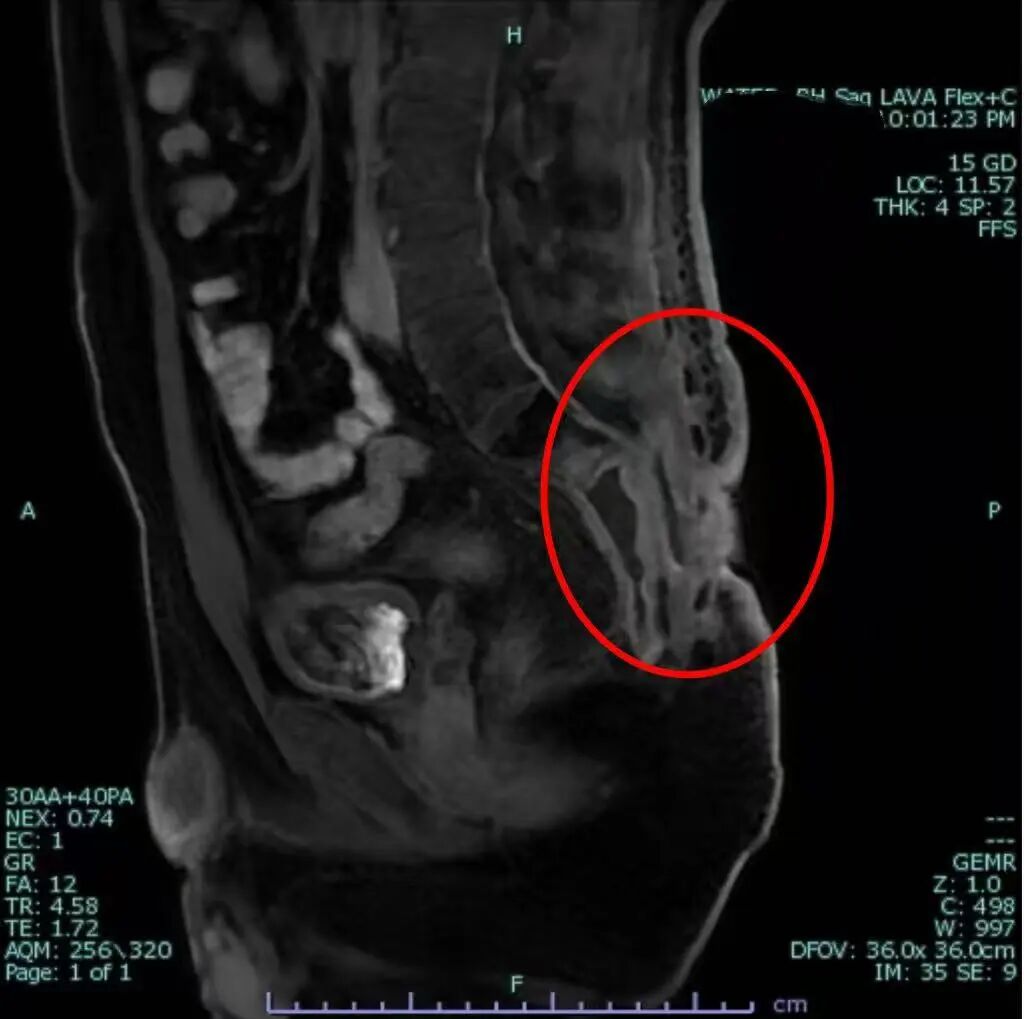

圖片

目前最新的盆腔核磁示:患者原骶尾部彌漫性異常信號(hào)較前基本消失

經(jīng)過幾個(gè)月的系統(tǒng)治療和精心照護(hù),奇跡開始顯現(xiàn)?;颊唠y以控制的劇痛和高熱癥狀逐漸消退,潰爛的傷口開始愈合,精神和食欲也一天天好起來。更令人欣喜的是,曾經(jīng)只能臥床呻吟的患者,如今已能自如地直立行走,實(shí)現(xiàn)了生活自理,臉上重現(xiàn)了久違的笑容,真正意義上回歸了家庭和社會(huì)生活。